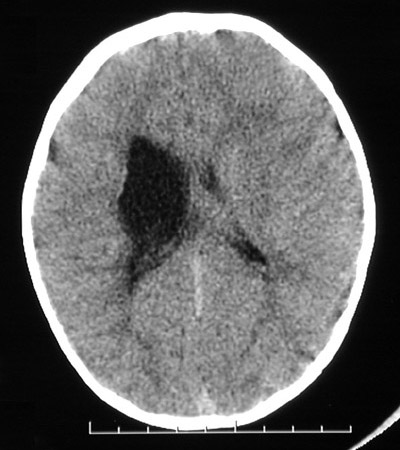

Here is a head CT scan revealing ex vacuo ventricular dilation in a case of cerebral palsy. The CT scan helps to rule out a more recent event such as trauma.